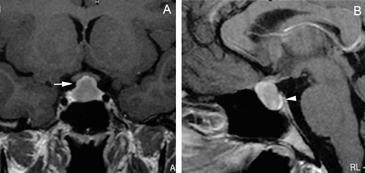

Figura 11A. Microadenoma pituitario productor de ACTH, corte coronal, secuencia T1w, muestra señal homogénea en la hipófisis. B. corte coronal (secuencia dinámica T1w con Gadolinio); se observa nódulo hipointenso de 3 mm (que aun no se refuerza) en cuadrante inferolateral izquierdo de la hipófisis (punta de flecha). C. corte coronal, secuencia tardía T1w con Gadolinio, muestra refuerzo heterogéneo de la glándula, no es posible precisar la ubicación del tumor. D. corte coronal, secuencia volumétrica SPGR T1w con Gadolinio de 1 mm de espesor, que muestra claramente la ubicación del tumor (punta de flecha). Esta secuencia ha mostrado mejores resultados en la evaluación de la enfermedad de Cushing.